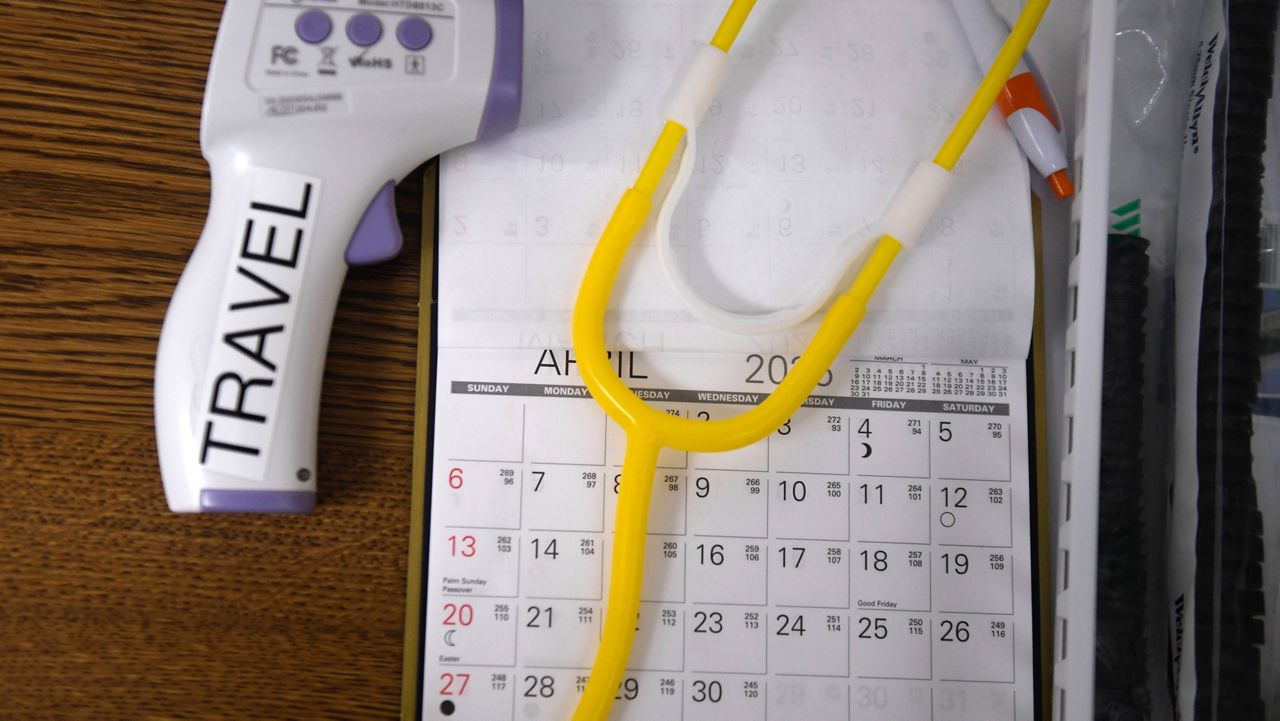

CONCORD, N.C. — If you’re looking for an at-home COVID-19 test, you might have a hard time.

These at-home options are on back order. Pharmacist Joe Moose, owner of Moose Pharmacy, says there are a few reasons.

Testing is ramping up as kids need it for school and people head back to workplaces.

He says he’s not sure when more at-home testing options could become available.

“We don’t know,” Moose said. "We are at the mercy of the manufacturers, how quickly they can make them, who they have made prior promises to, and then when they become available to us.”